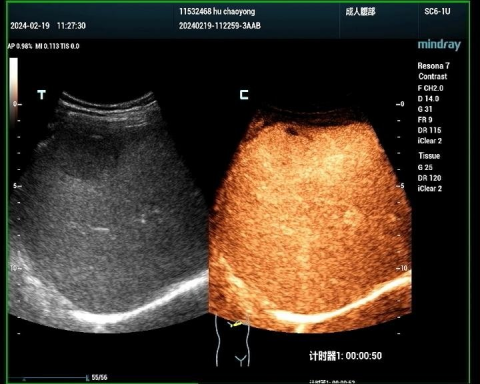

肝癌病例2